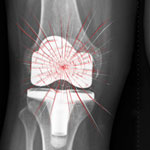

The plaintiff in the case states that she suffered from pain and injury following the implanting of the Zimmer NexGen CR-Flex devices in both left and right knees. She first had the surgeries performed in May of 2010. But by August of 2011, she required revision surgery on her right knee. In March of 2012, she needed revision surgery on her left knee.

“The High Failure Rate of a High-Flex Total Knee Arthroplasty Design,” a non-peer reviewed report issued in a 2010 and written by orthopedist Dr. Della Valle and Dr. Richard Berger, showed a 36 percent rate of the implant loosening with the patient needing revision surgery in 8.3 percent of those who received the Cr-Flex.